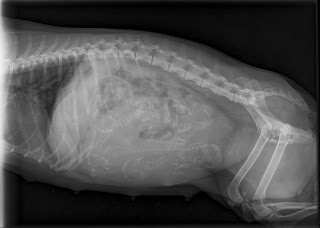

Viola "muutti" Marjolle jo pari viikkoa aikaisemmin, jotta ehti kotiutua hyvin Marjon luokse. Röntgenissä kävimme 14.2 ja kuvassa näkyi neljä pentua. Maanantaina 20.2 synnytys alkoi illalla, itse olin töissä iltavuorossa enkä ehtinyt kuin vasta klo 20 jälkeen paikalle. Onneksi näin viimeisen pennun syntymän ja sen miten hienosti Viola vauvojaa alkoi heti hoitamaan.